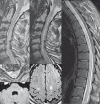

We describe a unique case of bilateral cervical spinal dural arteriovenous fistulas mimicking an intracranial dural arteriovenous fistula near the foramen magnum. We review its detection via MRI and digital subtraction angiography and subsequent management through surgical intervention. Pitfalls in diagnostic angiography are discussed with reference to accurate location of the fistula site. The venous anastomotic connections of the posterior midline spinal vein to the medial posterior medullary vein, posterior fossa bridging veins, and dural venous sinuses of the skull base are discussed with reference to problem-solving in this complex case. The mechanism of myelopathy through venous hypertension produced by spinal dural fistulas is also emphasized.